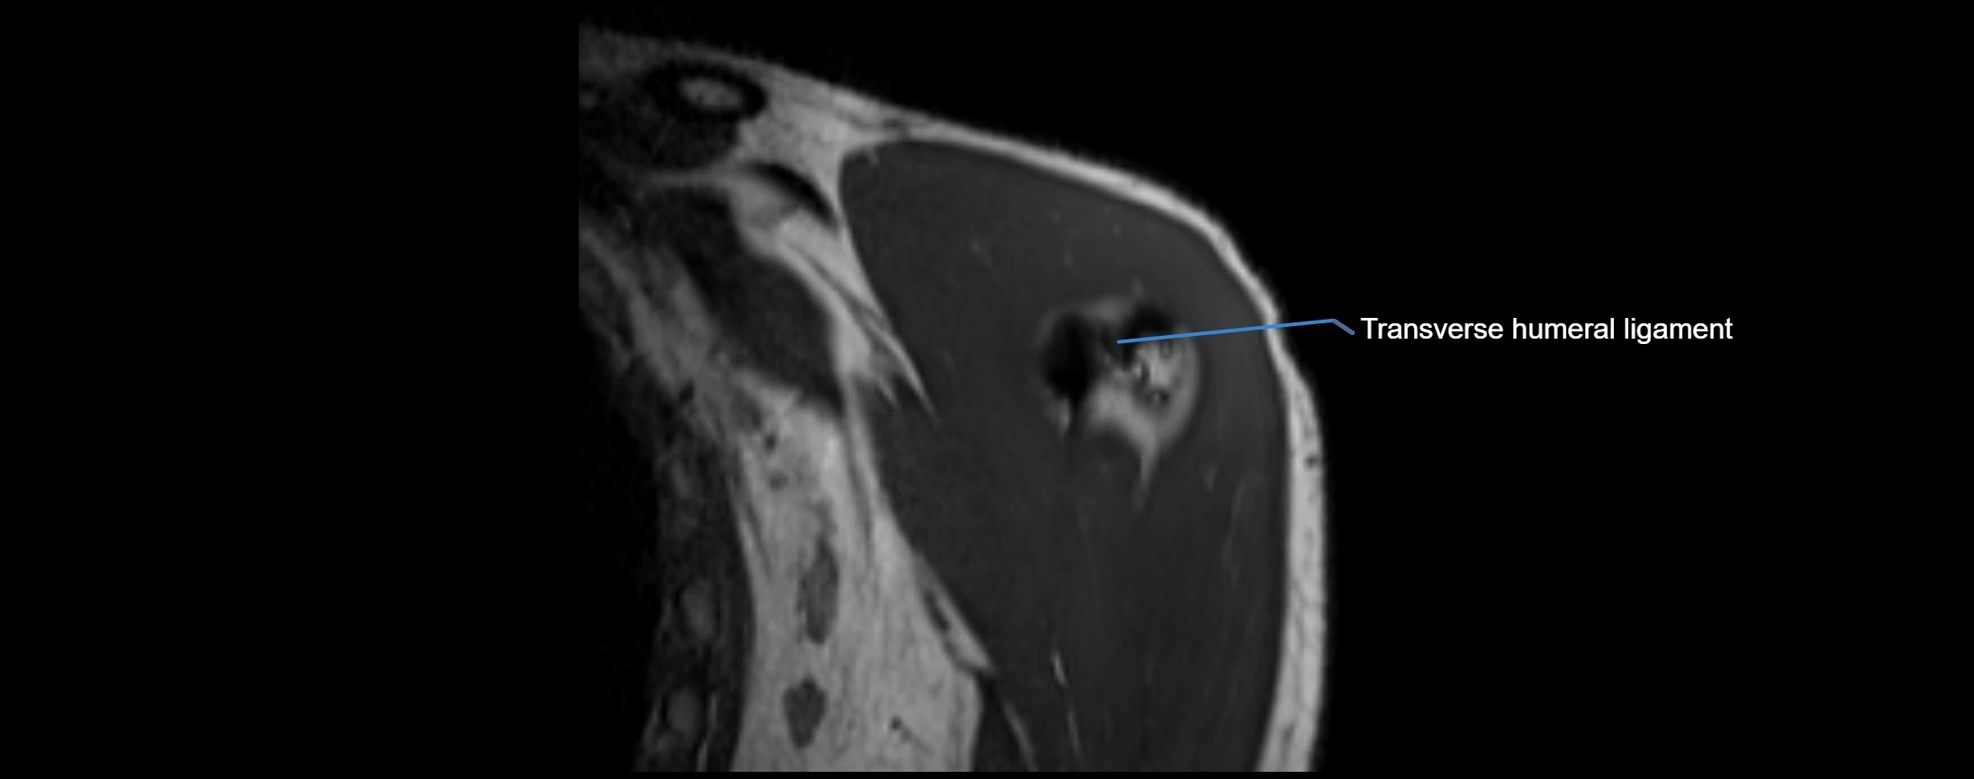

CT image

image